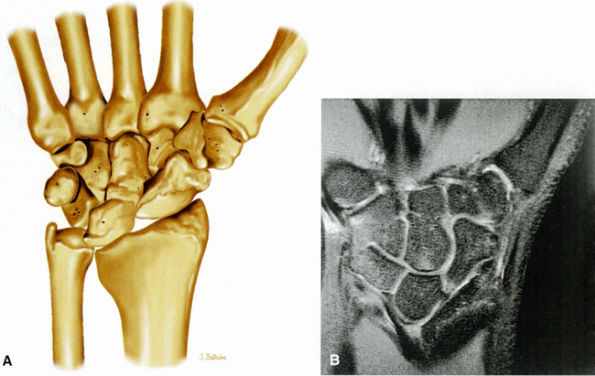

![]() |

FIGURE 10.73 ● Anatomy of the scapholunate ligament complex on three separate coronal images. (A) Volar component. (B) Membranous component. (C) Dorsal component. (D) On a corresponding axial image all three components of the scapholunate ligament complex are demonstrated. The dorsal scapholunate ligament is horizontally oriented and is perpendicular to the joint. The fibers of the membranous portion of the scapholunate ligament course peripherally and obliquely from the scaphoid downward toward the lunate in a dorsal-to-volar direction. The volar scapholunate ligament courses obliquely from the scaphoid downward to the lunate. This arrangement of scapholunate ligament fibers biomechanically hinges the joint dorsally at the level of the dorsal transverse fibers. In forced extension, scapholunate ligament failure initiates in its volar aspect. S, scaphoid; L, lunate; v, volar component; m, membranous component; d, dorsal component. Arrows correspond to the course of each component of the scapholunate ligament.